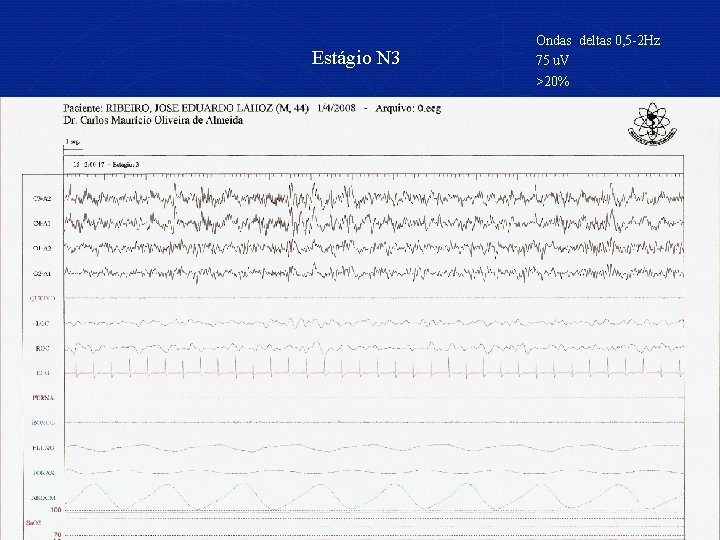

Estágio N 3 Ondas deltas 0, 5 -2 Hz 75 u. V >20%